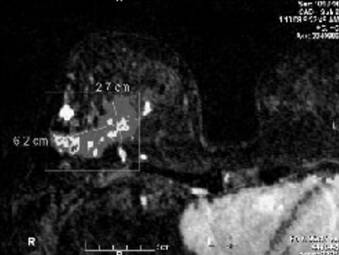

Figure 6

Note the measurements of the right breast mass per magnetic resonance imaging (MRI).

Figure 7

Bilateral breast MRI with gadolinium depicts the prominent right breast mass which overestimated the extent of disease. MRI measured the mass at 6.2 x 2.7 cm. Pathology measured the tumor at 1.8 cm.

A bilateral breast magnetic resonance imaging (MRI) showed a broad region (6.2 x 2.7cm) of abnormal enhancement in the right breast, which was suspicious for lobular carcinoma (Figures 6-7). To evaluate the extent of disease, we performed 3 MRI-guided core biopsies: 2 were negative for malignancy, and 1 revealed lobular carcinoma in situ. Thus, MRI was proven to overestimate her extent of disease secondary to her breast infections due to breast reduction.